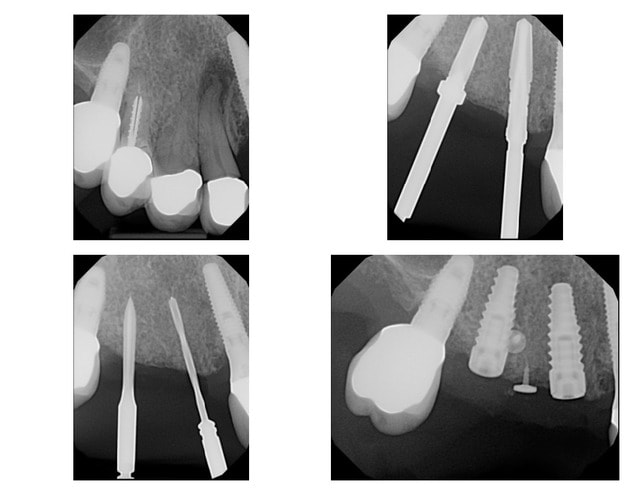

Le mélange BondBone + Mineros (pas de membranne) a très bien fonctionné, guérison parfaite.

Manipulation sympa, le BoneBond se transforme en pâte qui durcit en moins de 5 minutes (c'est du plâtre!).

Photo à 3 mois 1/2, aucune particule visible, densité osseuse très bonne

On voit bien l'angulation des implants déjà posés et des forêts initiaux.